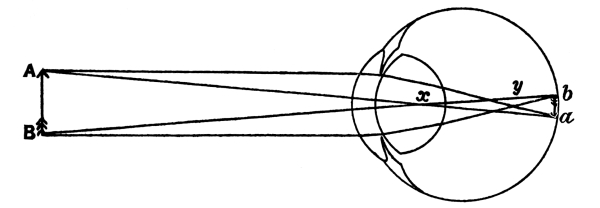

| 32. | Formation of an Image on the Retina | 391 |

| 33. | The Form of the Eyeball in Short Sight, Normal Sight,and Long Sight | 392 [Pg x] |